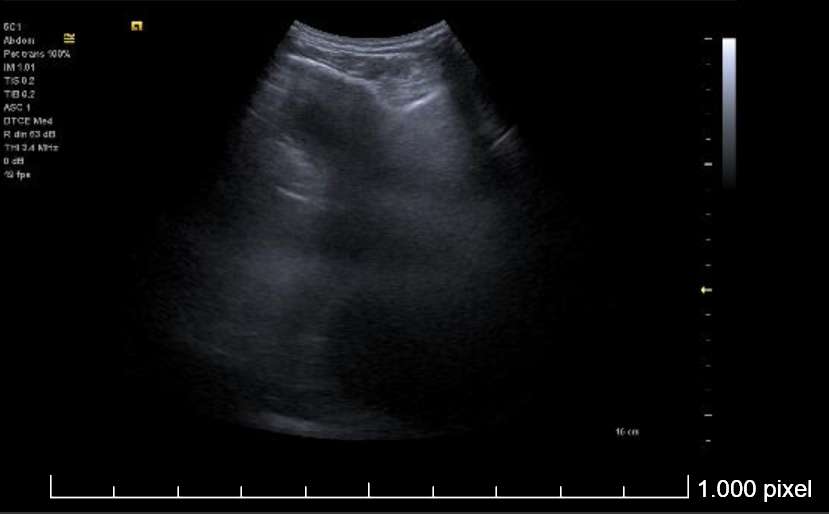

Derrame pleural izquierdo de 4 espacios intercostales, libre, hipoecogénico, sin ecos internos. Lóbulo pulmonar inferior izquierdo con imagen de patrón mixto (Intersticial y consolidación).

Se realiza toracocentesis diagnóstica y evacuadora con la paciente en decúbito lateral derecho. Se drenan un total de 550 cc en total de LP serohemático (pH en gasómetro 7.58).